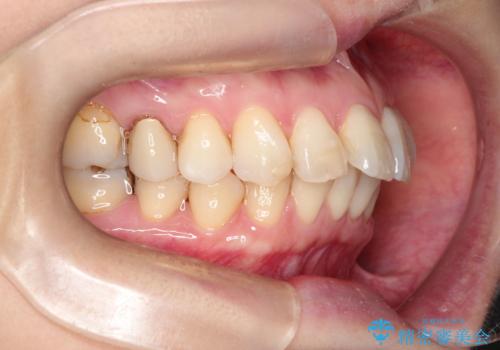

【インビザライン 】前歯を下げたい

- 前歯の凸凹と、前突を主訴に来院されました。

インビザライン にて治療を行なっております。

治療期間中はゴムかけを行なってもらうことで、前歯を下げることができました。